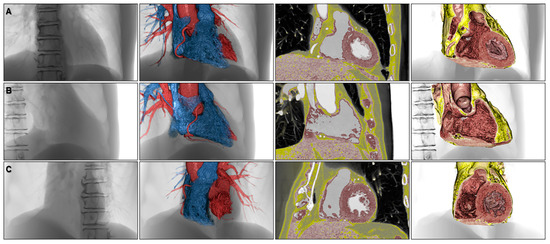

4. Educational Implication of the Three-Dimensional Living Heart Anatomy

5. Clinical Implication in Acquired Heart Disease with Representative Cases